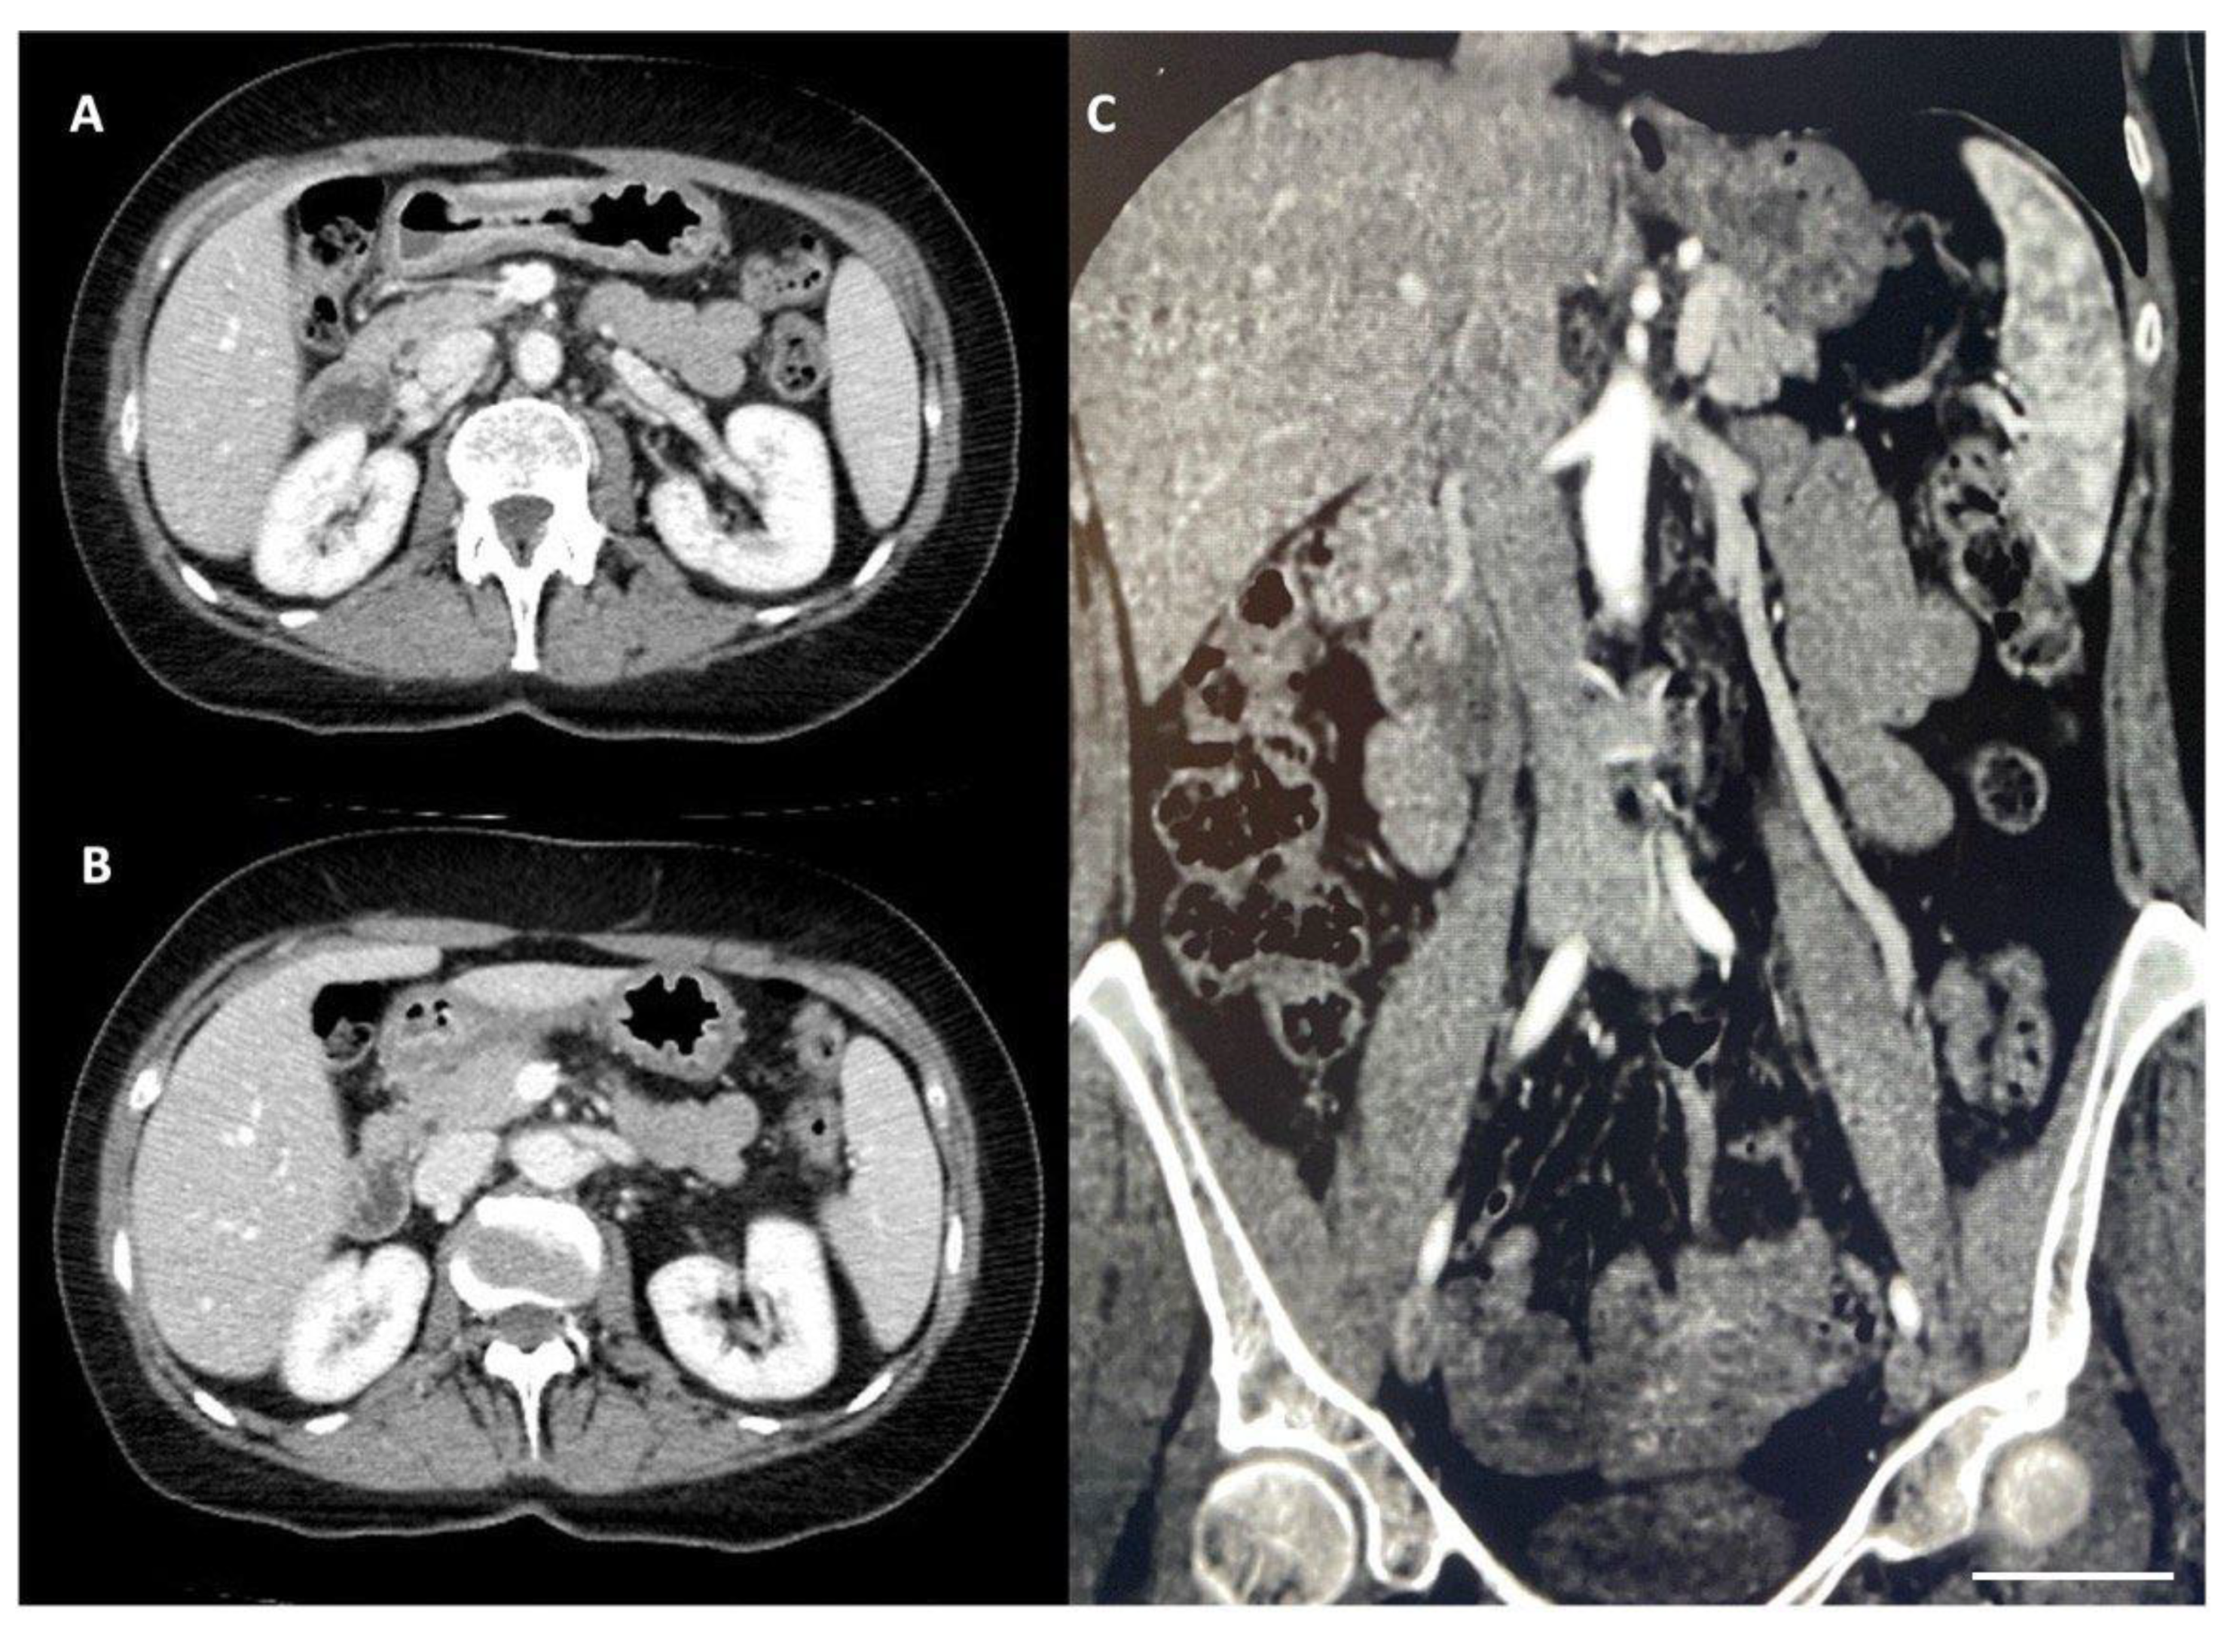

| Ober et al., 2022 [25] | 45-year-old female | Macroscopic hematuria, intermittent pain in the left flank and hypogastric region, postprandial nausea, and cachexia | Doppler US CT | Stent implantation in the LRV |